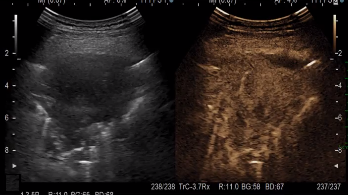

CEUS组对肺部病变内坏死的检测结果明显高于US组。确保了更好的诊断准确性,减少了非诊断性样本的机会。

CEUS引导活检的准确性为96.9%(34/35),而常规引导活检的准确性为32/40(80%)。